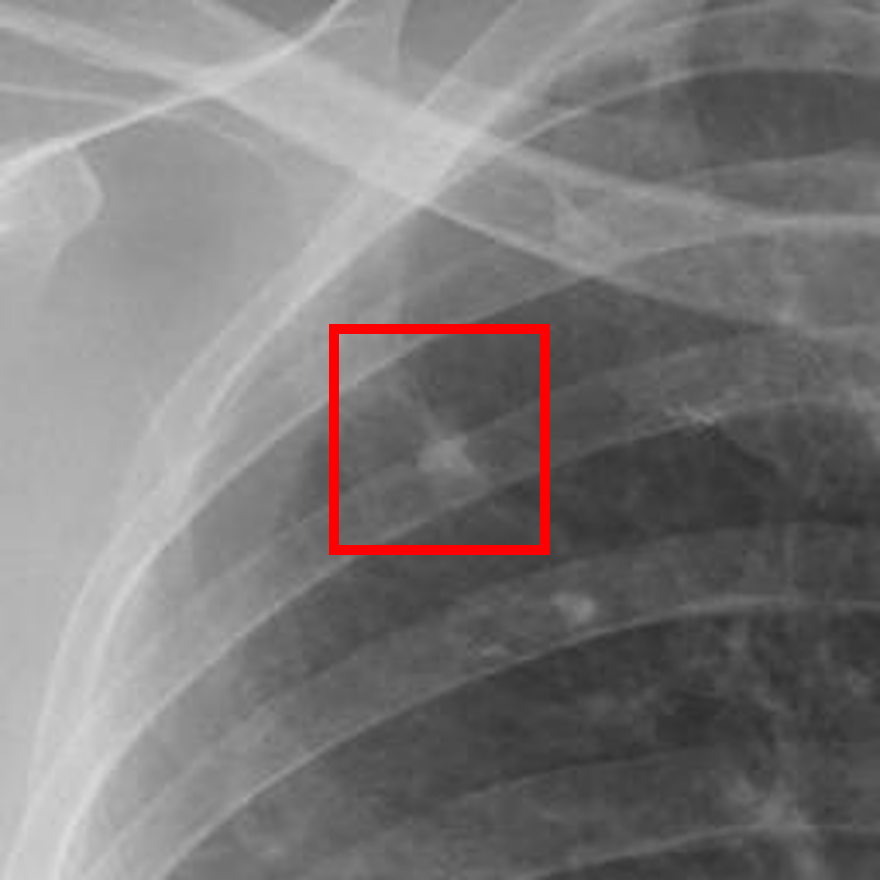

Refer to caption

(a) Healthy(1)

(b) NODE21

(c) Healthy(2)

(d) VinDr-CXR

Figure 5: Grad-CAM-based saliency maps illustrating model interpretability across datasets. Top row: Examples from NODE21 showing baseline (a) and curriculum-trained (b) models. Bottom row: Examples from VinDr-CXR demonstrating consistent attention patterns (c, d).

Grad-CAM visualizations showed that curriculum-trained models consistently focused on anatomically meaningful lung regions near nodules (Figure 5b), while baseline models activated broader, clinically irrelevant regions (Figure 5a). Similar attention patterns were observed across NODE21 and VinDr-CXR examples (Figure 5c,d), supporting interpretability and robustness.